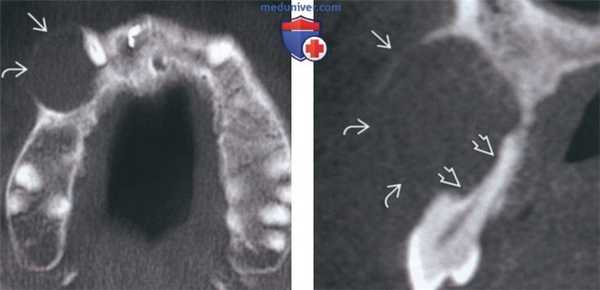

(Слева) На аксиальной КЛКТ в области правого клыка/премоляра определяется амелобластический рак. Обратите внимание на вздутие и перфорацию щечной кортикальной пластинки.

(Справа) Реформатированная КЛКТ альвелярного отростка у этого же пациента позволяет детально оценить вздутие и различимую глазом перфорацию щечной кортикальной пластинки, а также выраженную резорбцию корня 1-го премоляра.